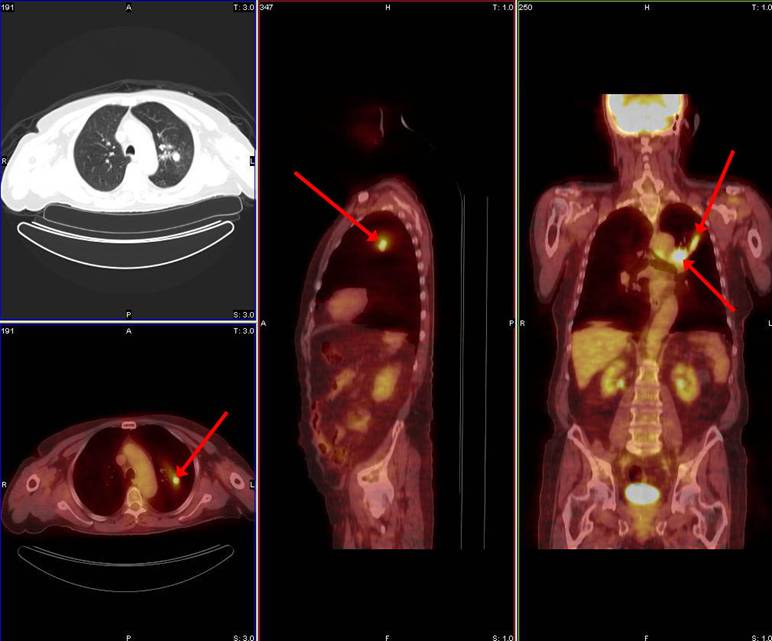

In 1998 a PET F-18 FDG study for solitary pulmonary nodules was successfully reimbursed by an insurance company

What are solitary pulmonary nodules?

Tumors that can be benign or malignant

Based on the PET scans, biopsies will only be done on the tumors that had high uptake of the FDG

Why were solitary pulmonary nodules reimbursed first by insurance companies?

Before, patients would biopsy all and every nodule that was found as probable for cancer

With solitary pulmonary nodules and PET, it allowed physicians to determine if the nodules were potentially cancerous and if biopsies were even needed – more cost effective

Breakdown what PET/CT is a combination of (what each part specifically scans)

PET – scans the patient’s physiology

CT – scans the patient’s anatomy

What type of process is commonly seen in cancer?

Metabolic process – hypermetabolic

What is metabolism?

The process of taking up glucose and using it as energy

Why do we like to use FDG as a pharmaceutical in PET?

It’s a sugar that is very similar to glucose

As cancer uses metabolic processes, it uses glucose as its main form of energy – we take advantage of this by binding the radioactive material with a pharmaceutical that’s similar in structure to glucose so that we can visualize where the cancer is based on its metabolism

What happens to the FDG when it’s up-taken by the cancer cells?

Instead of breaking down FDG and using it as energy, it will just accumulate in the cancer cell – makes the cancer more visible on our PET images